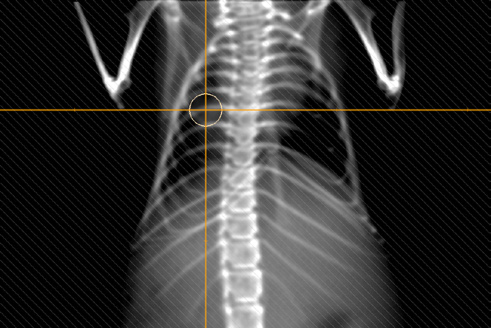

Figure 4. An example of a 3D-CRT mouse lung treatment plan consisting of 5 beams (image and plan from Institut Cancérologie de l’Ouest in Nantes, France). The dose calculation grid size is 0.2 mm and the dose uncertainty is roughly 0.5 % for each beam.

Two irradiation techniques are supported in μ-RayStation: 3D-CRT and static arc. 3D-CRT plans comprise of one or more beams with fixed angles and collimation for each beam (visualization of a beam can be seen in Figure 1. An example of a 3D-CRT treatment plan dose is displayed in Figure 4). Static arc plans comprise of one or more arc beams with fixed collimation and user specified start and stop gantry angles.

Figure 7. A digitally reconstructed radiograph for one of the beams on Figure 4.